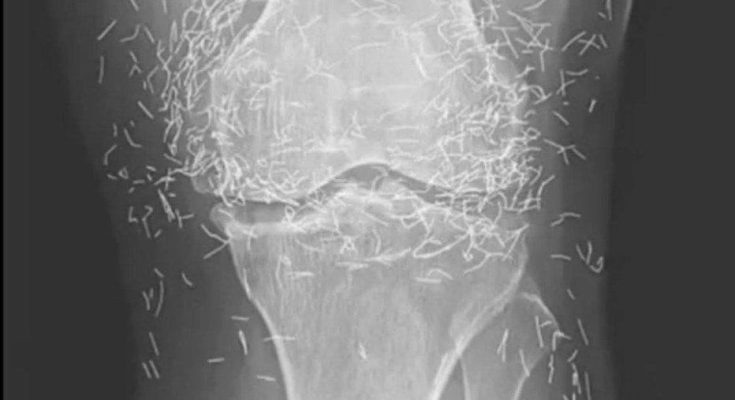

Years later, when doctors took X-rays to evaluate her knee condition, they weren’t prepared for what appeared on the images. Her knees were filled with dozens of bright, metallic flecks — tiny needles embedded deep within the joint area.

The findings were later documented in a case published by the New England Journal of Medicine.